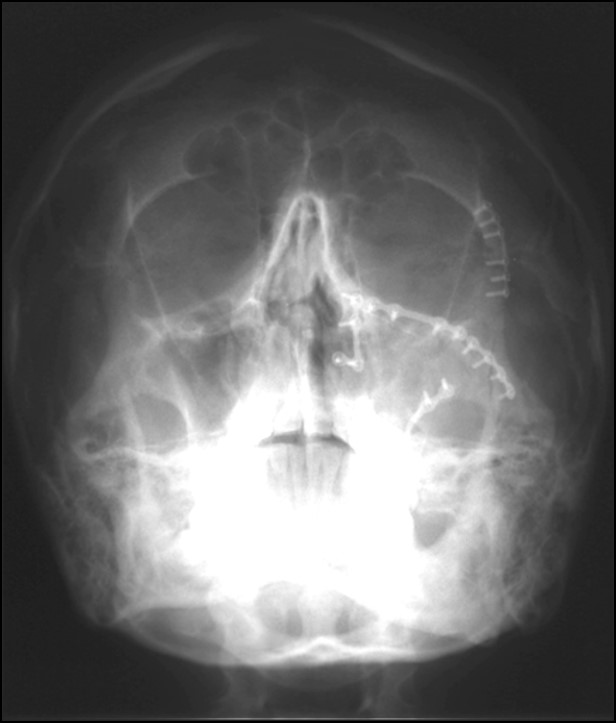

Ο γναθοπροσωπικός χειρουργός έχει, λοιπόν, πλατιά εκπαίδευση στην αντιμετώπιση τραυματικών κακώσεων του προσώπου, όπως είναι τα κατάγματα της άνω και κάτω γνάθου, του οφθαλμικού κόγχου, των ζυγωματικών οστών, του μετωπιαίου οστού και του ρινοηθμοειδικού συμπλέγματος, καθώς και των θλαστικών κακώσεων των μαλακών μορίων του προσώπου (Εικόνα 31Α, 31Β, 31Γ).